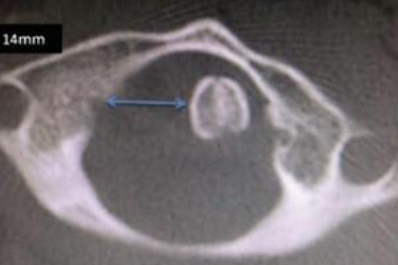

Como a Tomografia Computadorizada é usada na Síndrome de Grisel?

Fornece informações detalhadas sobre a posição das vértebras C1 e C2.

Quais são os sinais radiográficos importantes na Síndrome de Grisel?

Assimetria no espaço entre o odontóide e as massas laterais de C1 e o Wink Sign.